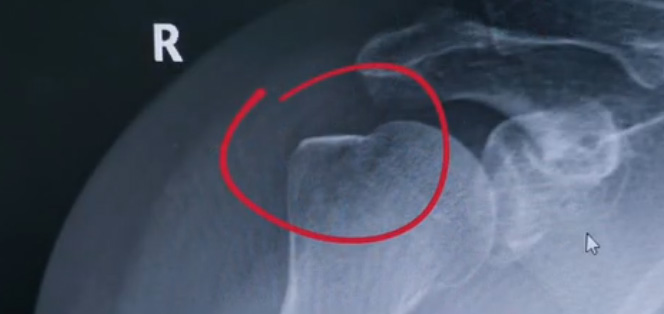

肩關(guān)節(jié)的X射線片子,看到?jīng)]有明顯的骨折,但是實際上已經(jīng)骨折了。那么是如何發(fā)現(xiàn)的呢?醫(yī)生對于做出疾病診斷的時候,會選擇什么樣的檢查方式。也更好的配合醫(yī)生,來解決問題。1米高的地方摔了下來,右側(cè)肩關(guān)節(jié)與地面相撞受傷了。當時的胳膊還能活動,疼痛感很明顯,但是在家觀察了一天,這個腫脹沒有明顯的加重。然而問題是什么呢?疼痛始終不能緩解,所以就需要到醫(yī)院檢查。醫(yī)生查看關(guān)節(jié)的受限也很明顯,尤其做外展這個動作的時候,幾乎沒辦法自行完成。肩關(guān)節(jié)內(nèi)的這個韌帶和肌腱可能還沒有發(fā)生嚴重的損傷。

首先做一個普通的X光檢查,看一看有沒有大的骨折或大的問題。結(jié)果是沒有發(fā)現(xiàn)太嚴重骨折損傷問題。結(jié)合病史,還是有點疑惑。因為疼的太厲害。x光檢查和他的疼痛之間不匹配,患者沒有骨頭的損傷,疼痛不至于達到這么嚴重的一個程度。是否有一種情況掩蓋住了病情。這也是X線檢查的通病。x光檢查它是一個二維的檢查,有可能患者肩關(guān)節(jié)啊發(fā)生了骨折。但是它的位置被前方或者側(cè)方的這個骨頭遮擋住了。不是立體的就沒辦法看到后方的情況。想要更加進一步的明確問題,判斷是否有骨頭的損害怎么辦?

進一步就是查CT,可以更全面的角度去判斷問題的所在。就會發(fā)現(xiàn)是否骨折可以看到確實存在著骨折,還好骨折不算嚴重??梢哉f是一個骨裂。這個肩關(guān)節(jié)與地面撞擊的時候,暴力沒有達到那么強。讓骨頭整個發(fā)生一個巨大的斷裂,而是造成了一個小的劈裂。適當?shù)倪M行一些抗炎止痛藥的使用。適當?shù)倪M行一些消腫治療,患者癥狀也就消失了。